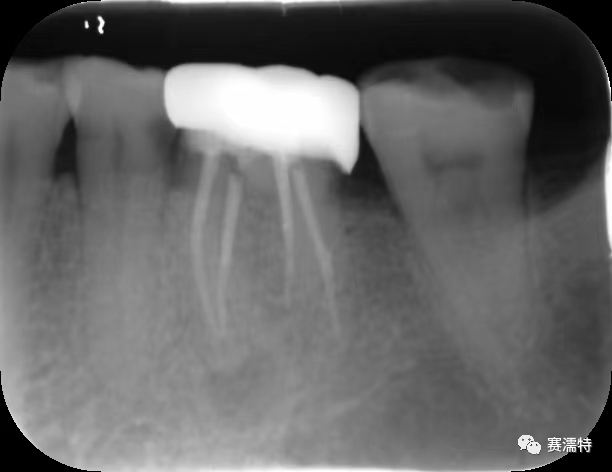

祝自洋老師案例